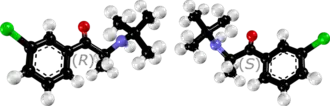

| Énantiomères S (en haut) et R (en bas) du bupropion | ||

| Nom UICPA | (RS)-1-(3-chlorophényl)-2-(tertbutylamino)propan-1-one | |

| Formule | C13H18ClNO [Isomères] |

| Masse molaire[1] | 239,741 ± 0,014 g/mol C 65,13 %, H 7,57 %, Cl 14,79 %, N 5,84 %, O 6,67 %, |

La dénomination commune internationale (DCI) « bupropione » est apparue en l'an 2000 en remplacement de sa dénomination originelle « amfébutamone », la molécule étant similaire à l'amphépramone (diéthylpropion), dans la classe des amphétamines.

Son nom chimique est β-keto-3-chloro-N-tert-butylamphetamine. C'est une cathinone substituée. Elle a donc un effet légèrement psychostimulant. Son mécanisme d'action est lié à l'inhibition de la recapture de la noradrénaline et de la dopamine. Elle se lie spécifiquement aux transporteurs de la dopamine, mais son effet comportemental a souvent été attribué à l'inhibition de la recapture de la noradrénaline. Il agit aussi comme antagoniste aux récepteurs nicotiniques de l'acétylcholine. Le bupropione appartient à la classe chimique des aminocétones et elle a une ressemblance avec les amphétamines et les phénéthylamines en général.